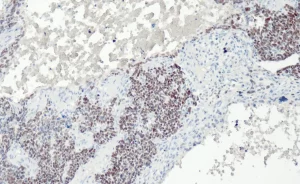

Melan A (A103)

Monoklonaler Mausantikörper

Melan A, auch bekannt als MART-1 (melanoma antigen recognized by T-cells 1), ist ein wichtiger immunhistochemischer Marker für die Diagnose des maglignomen Melanoms. Das Protein wird auf der Oberfläche von Melanozyten exprimiert und findet sich in normaler Haut, Netzhaut und Nävi.

Kontrolle: Melanom, Haut